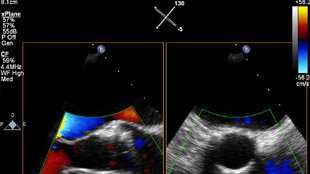

متابعة إجراءات التدخل وتقييمها من خلال الاتصالات الموسّعة بين أعضاء فرق طب القلب.